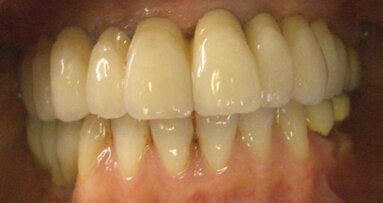

Fig. 9: Post-op retracted view.

The patient returned the following day. Her functional oc­clusion was evaluated, and her teeth were inspected for any re­sidual cement. Postoperative radiographs were taken to con­firm positive seating of the margins and the absence of any residual interproximal cement. Maxillary and mandibular alginate im­pressions were taken along with a polyvinylsiloxane bite reg­istration for fabrication of a maxillary full-arch bite guard for night-time wear.6 Postoperative home care instructions were given, and the patient was scheduled for a follow-up appoint­ment for additional photographic documentation, a final check for function and aesthetic evaluation, and delivery of the bite guard (Figs. 8 & 9).6